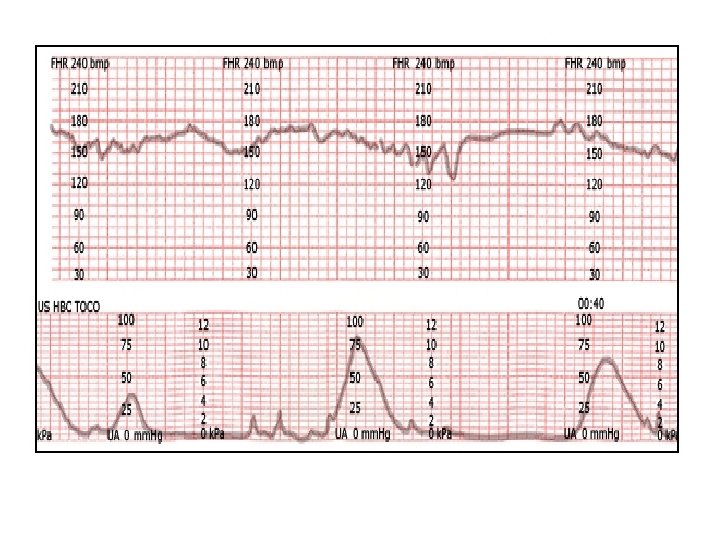

Variable decelerations with shoulder pattern